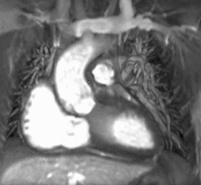

CMR in the 4 chamber view comparing the cine (left) with the late gadolinium image using inversion recovery (right). The subendocardial infarct is clearly seen. Fat around the heart also appears white.